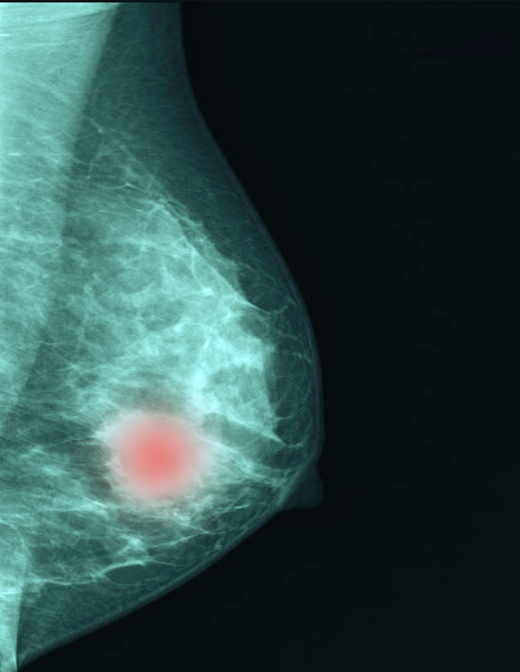

조기 유방암 환자에서 예후 진단 지표인 '온코타입Dx' 점수가 낮더라도, 암세포 활성도(Ki-67) 수치가 높다면 표적항암치료를 통한 적극적인 치료가 필요하다는 연구 결과가 발표됐다.

임상 현장에서 온코타입Dx와 Ki-67은 조기 유방암 환자의 예후를 예측하고, 항암 치료 여부를 결정하는 대표적인 지표로 활용된다. 온코타입Dx 검사상 25점을 기준으로 항암 여부를 결정하며, 종양세포의 증식과 관련된 핵단백질인 Ki-67 지수를 통해 종양의 공격성을 예측한다. 특히 호르몬 수용체 양성/HER2 음성 유방암에서 Ki-67이 높을수록 암 재발 가능성이 높거나 예후가 좋지 않은 것으로 알려졌다.

그 결과 Ki-67과 온코타입 점수는 중간 정도(R=0.455, P<0.001)의 상관관계를 보였으며, 온코타입Dx 점수가 낮은 환자에서 Ki-67이 높을수록 재발률이 높은 것을 확인했다. 또 Ki-67로 인한 재발은 '수술 3년 이내'보다는 '수술 3년 이후'에 더 높았으며, 이는 호르몬 치료의 저항성과 관련 있었다. 임상적으로 호르몬 치료에 저항성이 있는 것으로 분류되는 환자의 비율이 온코타입Dx 저위험군으로 항암 치료를 시행하지 않은 환자 가운데 Ki-67이 높은 군에서 통계적으로 유의미하게 높았다.

안성귀 교수는 "이번 연구는 온코타입Dx 저위험군 환자에서 Ki-67의 임상적 의미를 증명한 최초의 연구"라며 "높은 Ki-67은 호르몬 수용체 양성 유방암의 지연 재발과도 연관이 있는 만큼, 온코타입Dx상 저위험군이라 할지라도 Ki-67 수치가 높다면 지연 재발의 가능성을 염두에 두고 치료 방침을 상의하는 게 필요하다"고 말했다.

이어 "최근 조기 유방암 고위험군에서 두 가지 CDK4/6 표적치료제의 효과가 입증됐고, 해당 연구에서 높은 Ki67가 고위험군을 선별하는 데 활용됐다는 것을 고려했을 때, 이를 활용한 치료전략을 수립하기 위한 새로운 연구가 필요하다"고 강조했다.